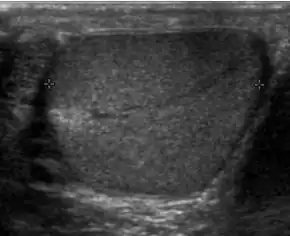

Patients with testicular lymphoma are usually old aged around 60 years of age, present with painless testicular enlargement and less commonly with other systemic symptoms such as weight loss, anorexia, fever and weakness. Bilateral testicle involvements are common and occur in 8.5% to 18% of cases. At sonography, most lymphomas are homogeneous and diffusely replace the testis [Fig. 7]. However focal hypoechoic lesions can occur, hemorrhage and necrosis are rare. At times, the sonographic appearance of lymphoma is indistinguishable from that of the germ cell tumors [Fig. 8], then the patient's age at presentation, symptoms, and medical history, as well as multiplicity and bilaterality of the lesions, are all important factors in making the appropriate diagnosis.